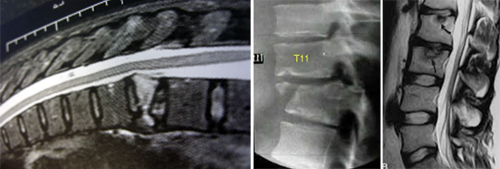

Έλεγχος

Για να γίνει κατανοητό τι πάσχει, χρειάζεται, γνώση της σχέσης οστού-δίσκων-νεύρων (άρα σχετική γνώση ανατομίας), κλινική εξέταση που προσδιορίζει την αιτία του πόνου και παρακλινικές εξετάσεις (ακτινογραφίες, αξονική ή μαγνητική τομογραφία).

Ο σπόνδυλος μπορεί να πάσχει από κάταγμα του σώματος λόγω οστεοπόρωσης ή πτώσης (ιδιαίτερα σε γυναίκες με οστεοπόρωση). Ο οστέινος δακτύλιος μπορεί να σπάσει σε ατύχημα. Το οστούν του σπονδύλου μπορεί επίσης να πονάει από βλάβη που προκαλεί μεταστατικός καρκίνος. Σε νεαρά ηλικία το σώμα του σπονδύλου μπορεί να υφίσταται παραμόρφωση από πίεση που την προκαλεί ο μεσοσπονδύλιος δίσκος (Schmorl).